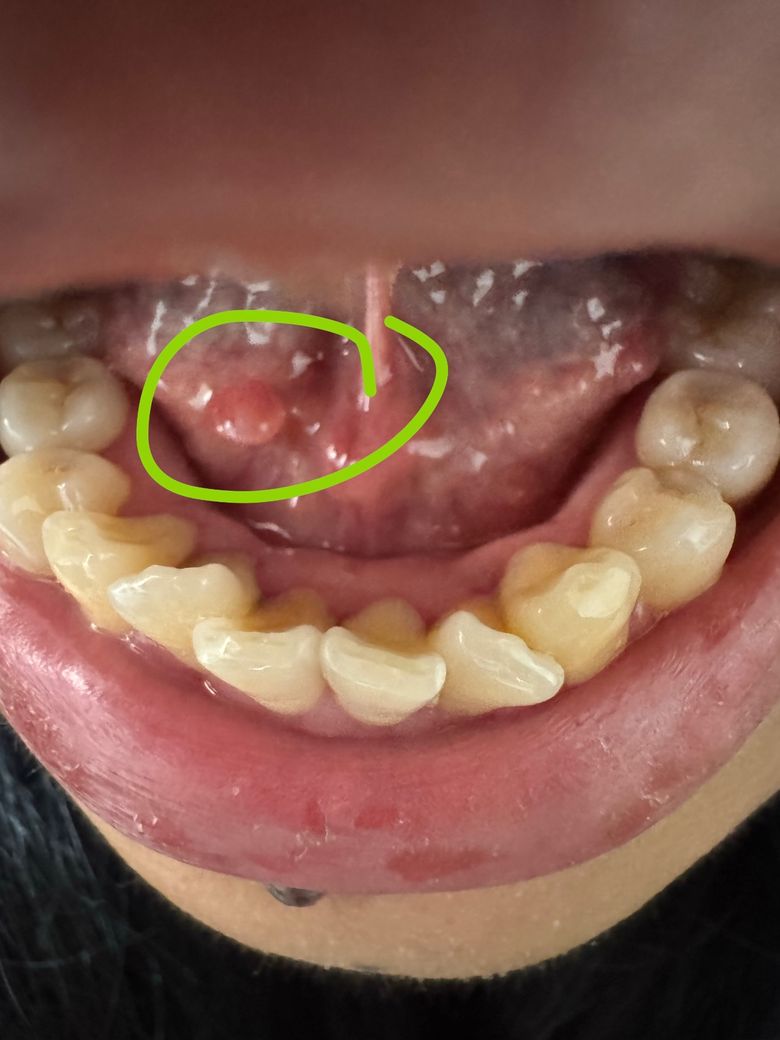

혀 밑 뭐가 났어요 혹 같은데 병원에 가야 하나요?

혀 밑, 입 안쪽에 작은 혹 같은 것이 생겼는데

아프거나 가렵지는 않습니다.

거의 2주정도 됐습니다.

혹시 병원에서 진료가 필요할까요?

혀 아래 점막에 작은 결절성 병변이 관찰되고 통증이 없다면 혀의 점막하 낭종 가능성이 가장 높습니다. 이러한 낭종성 질환은 증상이 없고 크기나 모양의 변화가 없다면 경과 관찰이 가능합니다. 하지만 통증 등의 증상이 발생하거나 크기가 증가하다면 수술적 제거가 필요할 수 있고 점막 표면의 궤양 등이 동반된다면 조직검사를 고려할 수도 있어 이러한 증상이 있다면 진료를 보시는 것을 권해드립니다.